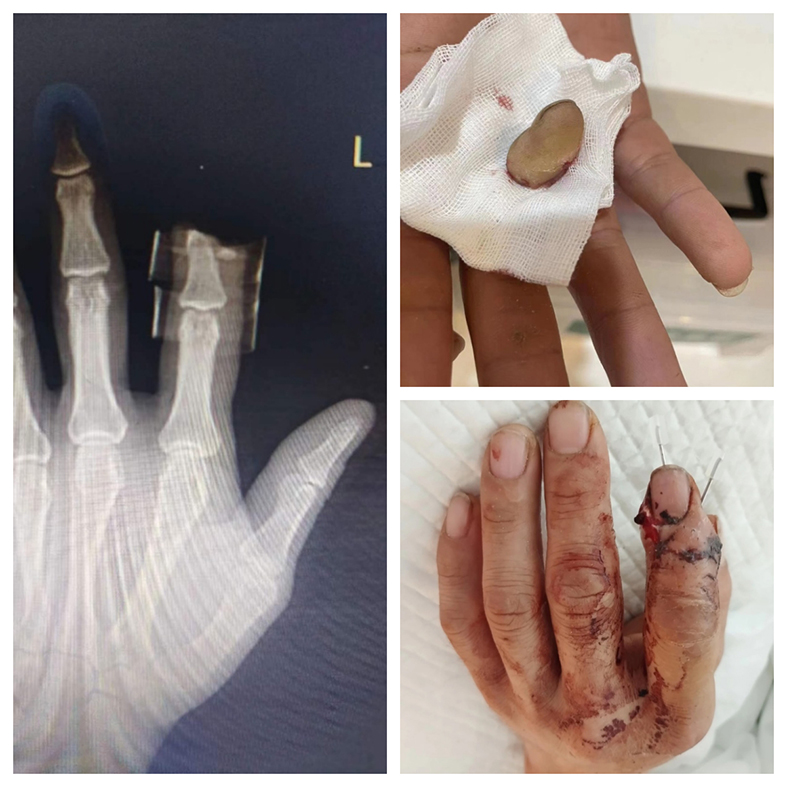

李某某,男,14岁,因外伤致右手中指远节完全离断。相比中节及近节手指的断指再植,远节手指的动脉及静脉极其纤细,约为0.1-0.2mm,哪怕在10倍显微镜的视角下依然细如发丝,术者需要在这样的血管下用比头发丝还细几倍的缝线在血管内缝合4针以上才能完全闭合血管,再植极其困难,成功率低,大多数医院选择残端修整,皮瓣覆盖缺损。但患者只有14岁,肢体的残疾会对患者的成长不利,会给患者造成较大的心理创伤,陈文忠果断选择断指再植术。术后,患者断指成活良好,患者及家属极其满意。

张某某,男,48岁,在工地干活时左手食指远节被机械夹掉。食指在手指中的作用相当大,对于患者的日常生活影响极其重要,且患者保手指的意愿极其强烈。陈文忠在显微镜下为患者吻合了2根动脉、3根静脉、2根神经。术后,断指成活良好,患者对手术效果表示满意。